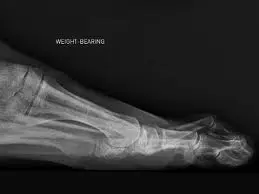

The metatarsophalangeal joint plantar plates are major stabilizers and form part of the plantar capsule. The plantar plates provide strength and support during ambulation. Disruption can lead to toe deformities. The normal plantar plate is a slightly hyper echoic broad-curved band, which protects the metatarsal head and inserts onto the proximal phalanx. Plantar plate tears typically appear as hypo echoic defects. The torn plantar plate is often swollen and hyper vascular in the acute phase of degeneration.

A Morton’s neuroma is caused by mechanical damage to the interdigital nerve, resulting in perineural fibrosis. On ultrasound it commonly appears as an ovoid hypo echoic mass, although the shape and echogenicity may vary. Intermetatarsal bursitis appears as a hypo echoic or anechoic zone in a normally echogenic webspace, generally dorsal to the interdigital nerve, although sometimes enveloping it. This soft tissue collection may become complex and heterogeneous with time. Dynamic assessment of a webspace will show poor compressibility of a neuroma and high compressibility of a bursitis (note: complex bursa may mimic a neuroma). Treatment options include ultrasound guided cortisone or alcohol injection.

Common causes of forefoot pain include joint inflammation (arthritis, capsulitis & synovitis), plantar plate tears, tendinosis (“tendinitis”), bursitis and Morton’s neuroma. A Morton’s neuroma occurs when scar tissue builds upon a nerve in between the toes known as the interdigital nerve (nerve between the digits, or toes). In Morton’s entrapment, the common plantar digital nerve, also referred to as the intermetatarsal nerve, gets compressed from forefoot plantar pressure in the late midstance and propulsive phases of gait against the distal margin of the transverse intermetatarsal ligament This is most frequently seen in women and is and is attributed to high heeled shoes. The pain is often severe and has an electric shock character to it. Common symptom descriptions include some or all of the following: “It feels like my sock is wadded up under my foot,” “cramping,” “numbness,” “burning,” “radiating sensations into the adjacent toes,” “the inability to walk barefoot on a hard floor,” and “tingling.” Others describe a feeling like having a pebble in their shoe or walking on razor blades.

Symptoms includes: pain on weight bearing, frequently after only a short time. The nature of the pain varies widely among individuals. Some people experience shooting pain affecting the contiguous halves of two toes. Burning, numbness, and paresthesia may also be experienced. Usually, patients with Morton’s entrapment demonstrate pain with plantar palpation of the interspace between the metatarsal heads.